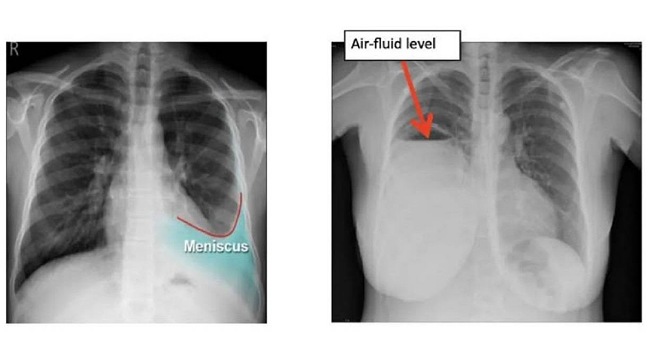

รศ.นพ.ศิระ เลาหทัย แพทย์ผู้เชี่ยวชาญศัลยศาสตร์ ทรวงอกเฉพาะทางด้านการผ่าตัดส่องกล้องในช่องทรวงอก โรงพยาบาลวชิรพยาบาล กล่าวว่า ภาวะ “น้ำในเยื่อหุ้มปอด (Pleural effusion) ” คือภาวะที่มีของเหลวสะสมอยู่ในช่องเยื่อหุ้มปอด (ระหว่างเยื่อหุ้มปอดชั้นในที่คลุมปอดกับเยื่อหุ้มปอดชั้นนอกที่ติดกับผนังอก) สามารถเกิดได้จากหลายสาเหตุ โดยปกติมักเกิดจาก 2 ประเภทใหญ่ตามลักษณะของสาเหตุที่เกิดขึ้น โดยในกลุ่มแรกมักเกิดจากโรคประจำตัว (Transudative Pleural Effusion) โดยเกิดจากความดันในหลอดเลือดผิดปกติหรือโปรตีนในเลือดต่ำ ของเหลวที่รั่วออกมาจะใส มีปริมาณโปรตีนต่ำ ซึ่งมักจะเป็นสาเหตุหลัก ของโรคภาวะหัวใจวาย (Congestive heart failure), โรคตับแข็ง (Cirrhosis),โรคไต (Nephrotic syndrome) ซึ่งโรคประจำตัวเหล่านี้สามารถรักษาได้ โดยปรับปริมาณน้ำในร่างกายให้เหมาะสม ร่างกายจะค่อย ๆ ดีขึ้น

ในกลุ่มที่สองเกิดจากตัวปอดเอง (Exudative Pleural Effusion) ซึ่งมักจะเกิดจากมะเร็ง (เช่น มะเร็งปอด, มะเร็งเต้านมกระจายมาที่เยื่อหุ้มปอด), วัณโรคปอด (Tuberculosis), ปอดติดเชื้อ (Pneumonia) อันเกิดจากเยื่อหุ้มปอดอักเสบหรือมีการอุดตันของระบบน้ำเหลือง รวมถึงของเหลวที่มีโปรตีนสูงและเซลล์อักเสบจำนวนมาก โดยการรักษานั้น หากเกิดจากมะเร็งเราสามารถเอาน้ำออกแล้วใส่ยาเคลือบปอดเพื่อป้องกันการกลับมาเป็นซ้ำได้ (chemical pleurodesis) และในส่วนของกลุ่มที่เกิดภาวะติดเชื้อ เช่น วัณโรคหรือปอดติดเชื้อ หากดำเนินการรักษาแก้อาการของตัวโรค โดยลดอาการบวมน้ำลง อาการก็มักจะดีขึ้นตามมา แต่อาการที่พบในผู้ป่วยอยู่บ่อยครั้ง เช่น มีอาการหายใจลำบาก, มีภาวะเจ็บหน้าอก (โดยเฉพาะเวลาหายใจลึก ๆ) หรือไอแห้ง ๆ มีน้ำเสียงลดลง เหล่านี้แพทย์มักจะวินิจฉัยว่าเกิดจากน้ำในเยื่อหุ้มปอด ซึ่งสามารถใช้การเอกซเรย์ทรวงอก, อัลตราซาวด์ หรือ CT scan และอาจมีการเจาะน้ำในเยื่อหุ้มปอด เพื่อนำไปตรวจหาสาเหตุที่แน่นอน ทั้งนี้การวินิจฉัยน้ำในเยื่อหุ้มปอดนั้น สามารถนำหลักการรักษาน้ำในเยื่อหุ้มปอดให้เป็นปกติได้โดย 1.รักษาตามสาเหตุที่ทำให้เกิดน้ำที่ทำให้เกิดภาวะหัวใจวาย(CHF) โดยส่วนใหญ่จะให้ยาขับปัสสาวะเพื่อลดน้ำในร่างกาย แต่หากผู้ป่วยเป็นวัณโรค ก็จะให้ยาต้านวัณโรคครบสูตร 6-9 เดือน ส่วนผู้ป่วยที่ป่วยเป็นโรคมะเร็ง แพทย์ผู้รักษาจะพิจารณาให้เคมีบำบัด ทำการระบายของเหลวร่วมกับใส่สารเคลือบเยื่อหุ้มปอด(Pleurodesis) เพื่อป้องกันการกลับมาเป็นซ้ำ ส่วนอีกอาการหนึ่งคือ หากเกิดอาการติดเชื้อ เช่น เกิดภาวะปอดบวม แพทย์ผู้ทำการรักษาจะให้ยาปฏิชีวนะร่วมด้วย